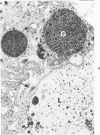

A naturally occurring cardiomyopathy (round heart disease) which is potentiated by inbreeding and a cardiomyopathy produced by furazolidone, a nitrofuran derivative, were studied for an associated alpha1-antitrypsin deficiency in two flocks of turkeys (one inbred for round heart disease and a commercial flock). At 4 weeks of age, the furazolidone-fed birds of both flocks demonstrated a marked increase in mortality and cardiac dilatation associated with disordered hepatic metabolism when compared with controls. Although PAS-positive, diastase-resistant globules were observed in the livers of both strains of turkeys fed furazolidone, these globules were present in lysosomes and not in the rough endoplasmic reticulum as in alpha1-antitrypsin deficiency. The control inbred birds with round heart disease did not demonstrate histologic or biochemical evidence of an alpha1-antitrypsin deficiency. It is proposed that furazolidone in the turkey produces primary hepatic damage that is reflected in lowered total serum proteins, including trypsin inhibitory capacity, and that the alterations produced by furazolidone are superimposed on round heart disease in the inbred flock.